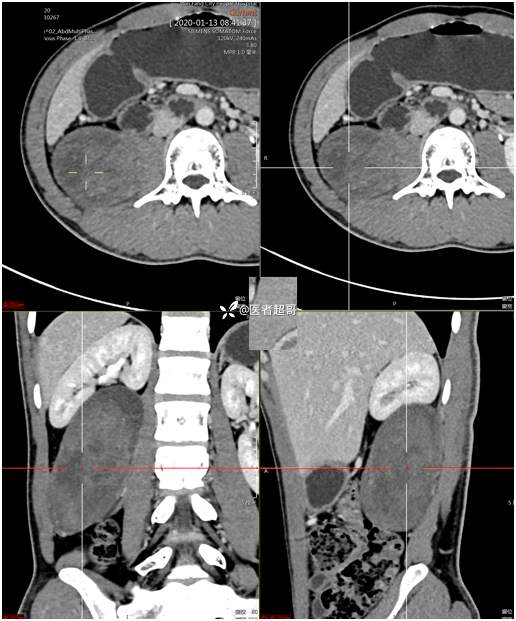

【影诊笔记754】腰痛就诊,腹膜后实性占位,请诊断分析!

现病史:患者2月前无明显诱因出现腰背部疼痛,夜间为著。患者无头痛、头晕,无恶心、呕吐,无胸闷、憋气,无腹痛、腹胀。无尿频、尿急、尿痛等现象。患者在院外未作特殊治疗。为求进一步诊疗,来我院肾内科门诊就诊。门诊行双肾、输尿管、膀胱(前列腺)彩超提示:腹膜后实性占位。患者遂来我科就诊。我科以“腰痛”收治入院,患者自发病以来,神志清,精神可,饮食可,睡眠差。小便如上述,大便未见明显异常。体重无明显增减。